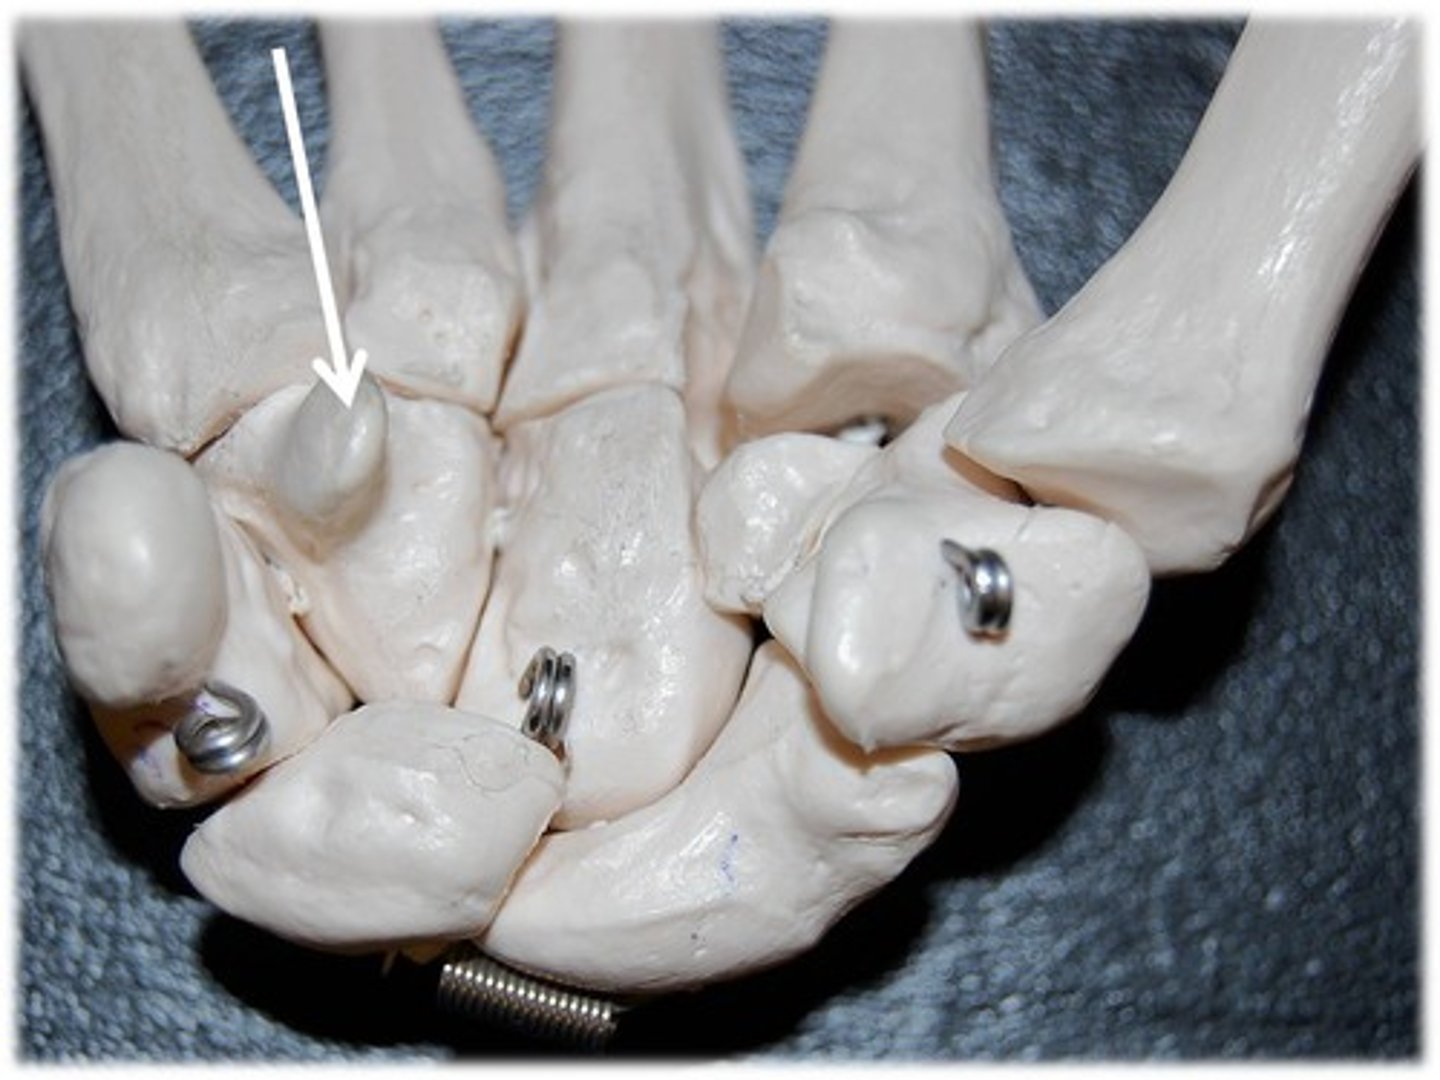

metacarpals

1st metacarpal

ID bone

1st proximal phalanx

ID bone

4th proximal phalanx

ID bone

3rd proximal phalanx

ID bone

4th metacarple

ID bone

metacarpals

ID bone group

phalanges

ID bone group

proximal phalanges

ID GREEN bones

middle phalanges

ID BLUE bones

distal phalanges

ID red bones

metacarpal

ID YELLOW bones